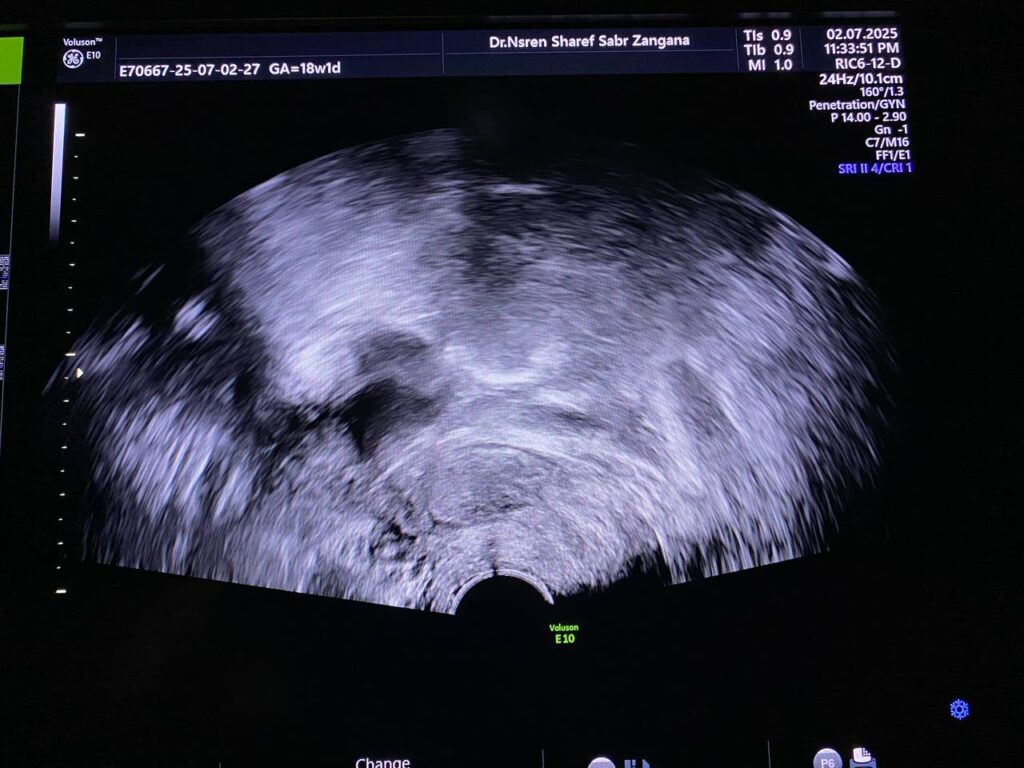

· Right ovary contain avascular circumscribed cystic mass 38x38mm , mostly physiological, for follow up